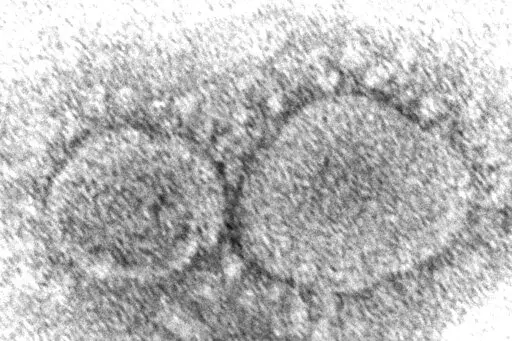

Workers at a drive-up COVID-19 testing clinic stand in a tent as they prepare PCR coronavirus tests, Jan. 4, 2022, in Puyallup, Wash., south of Seattle. Testing for COVID-19 has plummeted across the globe, dropping by 70 to 90% worldwide from the first to the second quarter of 2022, making it much tougher for scientists to track the course of the pandemic and spot new, worrisome viral mutants as they emerge and spread. (AP Photo/Ted S. Warren, File)